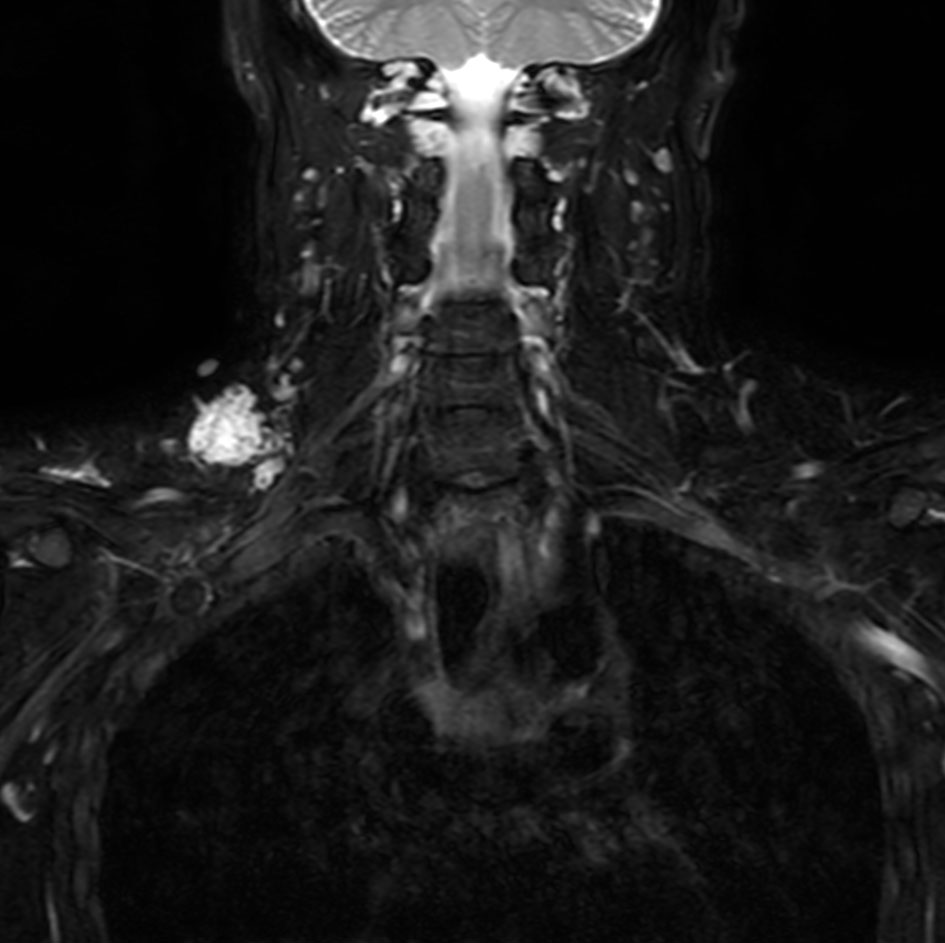

Coronal T2w VISTA